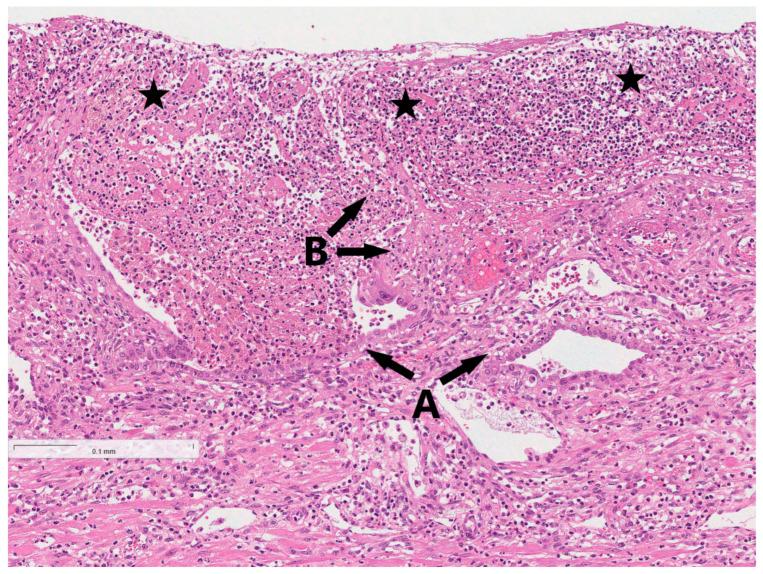

() and () are rare etiological factors for postpartum endometritis and are typically associated with bacterial vaginosis. However, in some cases, and can cause serious postpartum endometritis with complications such as sepsis. 26-year-old pregnant woman expecting monochorionic diamniotic twins presented to the hospital at 35 weeks and 3 days of gestation and two male infants were delivered via the Cesarean section. On the fifth day after delivery, the patient began to complain of intense abdominal pain, a fever of 37.9 °C, and overall weakness. Blood tests revealed neutrophilic leukocytosis, increased C-reactive protein (CRP) of 225.4 mg/L. Upon examination, abdominal distension, tenderness on palpation, and positive symptoms of peritoneal irritation were present and the site of the abdominal incision was inflamed with flowing foul-smelling greenish pus. Ultrasound examination revealed free fluid collection in the peritoneal cavity, under the liver, and around the uterus. Later, the condition of the patient worsened with progressing hypotension and respiratory distress. As a result, suppurative peritonitis and sepsis was suspected and the patient underwent urgent total hysterectomy without oophorectomy. Acute endometritis, focal myometritis, and chronic cervicitis were concluded from histopathological examination of the removed uterus. Microbiological tests showed the most abundant growth of in the wound cultures and great abundance of in the abdominal cavity cultures. After trying three different treatment schemes and difficulties with determining the antibiotic sensitivity tests for pathogens, the antibacterial therapy was escalated to Meropenem, which was found to be effective, and the patient was discharged home. This case report highlights the severity of complications of postpartum endometritis that can be caused by rare pathogens (such as and ), and strategies for how to manage it. The clinical presentation of a patient should be monitored closely for several days after Cesarean section and if endometritis is suspected, microbiological cultures are necessary to determine the cause of infection and implement an appropriate treatment.

()和()是产后子宫内膜炎的罕见病因,通常与细菌性阴道病有关。然而,在某些情况下,()和()可导致严重的产后子宫内膜炎并伴有败血症等并发症。一名怀有单绒毛膜双羊膜囊双胞胎的26岁孕妇在妊娠35周零3天时入院,通过剖宫产分娩出两名男婴。产后第五天,患者开始抱怨剧烈腹痛、发热37.9°C以及全身无力。血液检查显示中性粒细胞增多,C反应蛋白(CRP)升高至225.4mg/L。检查时,出现腹胀、触诊压痛以及腹膜刺激征阳性,腹部切口部位发炎并有恶臭的绿色脓性分泌物。超声检查显示腹腔、肝脏下方和子宫周围有游离液体聚集。后来,患者病情恶化,出现低血压和呼吸窘迫加重。因此,怀疑为化脓性腹膜炎和败血症,患者接受了紧急全子宫切除术,未切除卵巢。切除子宫的组织病理学检查结果为急性子宫内膜炎、局灶性子宫肌炎和慢性宫颈炎。微生物学检测显示伤口培养物中()生长最为丰富,腹腔培养物中()大量存在。在尝试了三种不同的治疗方案且难以确定病原体的抗生素敏感性试验后,抗菌治疗升级为美罗培南,发现有效,患者出院回家。本病例报告强调了由罕见病原体(如()和())引起的产后子宫内膜炎并发症的严重性以及如何处理的策略。剖宫产术后应密切监测患者的临床表现数天,如果怀疑有子宫内膜炎,需要进行微生物培养以确定感染原因并实施适当的治疗。